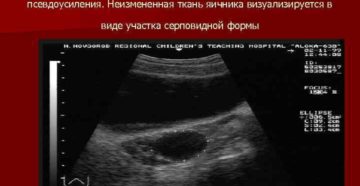

Анэхогенное образование в яичнике или киста понедельник, апреля 25, 2016 — 14:21 Анэхогенное образование в…